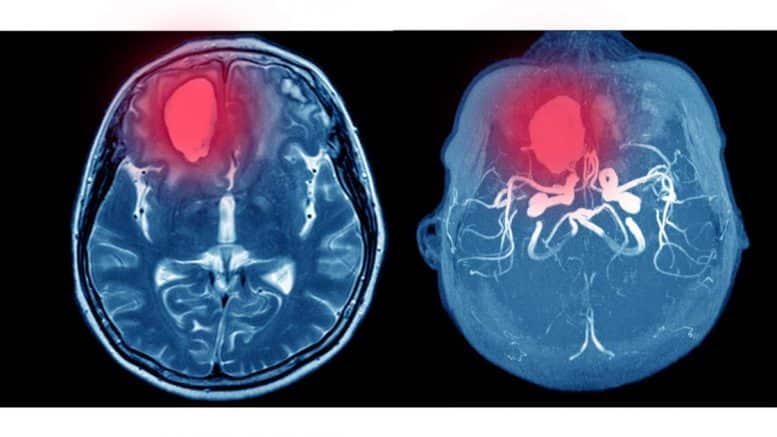

Non-traumatic intracranial hemorrhage includes non-traumatic types of subarachnoid hemorrhage, intracerebral hemorrhage, and subdural hematoma. (2)

Intraparenchymatous hemorrhage (IPH), the deadliest type of stroke, is commonly presented along with an acute, moderate to high-intensity headache. Patients may present with a history of uncontrolled hypertension, anticoagulant or antiplatelet drug use, previous cerebral infarction, coagulopathy, vasculitis, substance abuse, especially cocaine and alcohol, and smoking. Patients with IPH may be young patients with uncontrolled hypertension, a history of vascular malformations, or elderly patients with coagulopathy, a group in which amyloid angiopathy is common. Important features to assess are decreased level of consciousness, airway compromise, uncontrolled hypertension, coagulopathy, neurological deficit, and previous underlying condition (cerebral infarction, vascular malformations, cerebral tumors). Although these patients may have florid presentations, they could also present oligosymptomatic. (2, 28, 29, 30)

Aneurysmatic subarachnoid headache (SAH) is one of the most concerning differentials. It should be suspected in young or mid-aged patients with a family or personal history of aneurysms, previous aneurysms, or smoking, one of the most common well-known risk factors for aneurysmal formation and progression. Patients could present with alterations in the level of consciousness, meningeal signs, neck stiffness, and neurological deficits. Further, there have been reported cases of milder forms of pain and no neurological findings. Clinical suspicion takes the lead when considering this differential, especially in non-typical cases. (2, 31-33)

Intraparenchymatous Hemorrhage: (54)

- ABCDE approach and stabilization.

- Perform a focused neurological assessment and fundoscopy.

- Head elevation to 30º if suspected or confirmed cerebral edema.

- Urgent head CT without contrast.

- Cautiously lower BP to SBP <150mmHg.

- Order labs including CBC, metabolic panel, Blood Gases and electrolytes, coagulation panel, and cardiac troponin.

- Antiedema measurements if needed.

- Neurosurgical consultation.

- Disposition: ICU or Neuro ICU. Possible neurosurgical intervention.